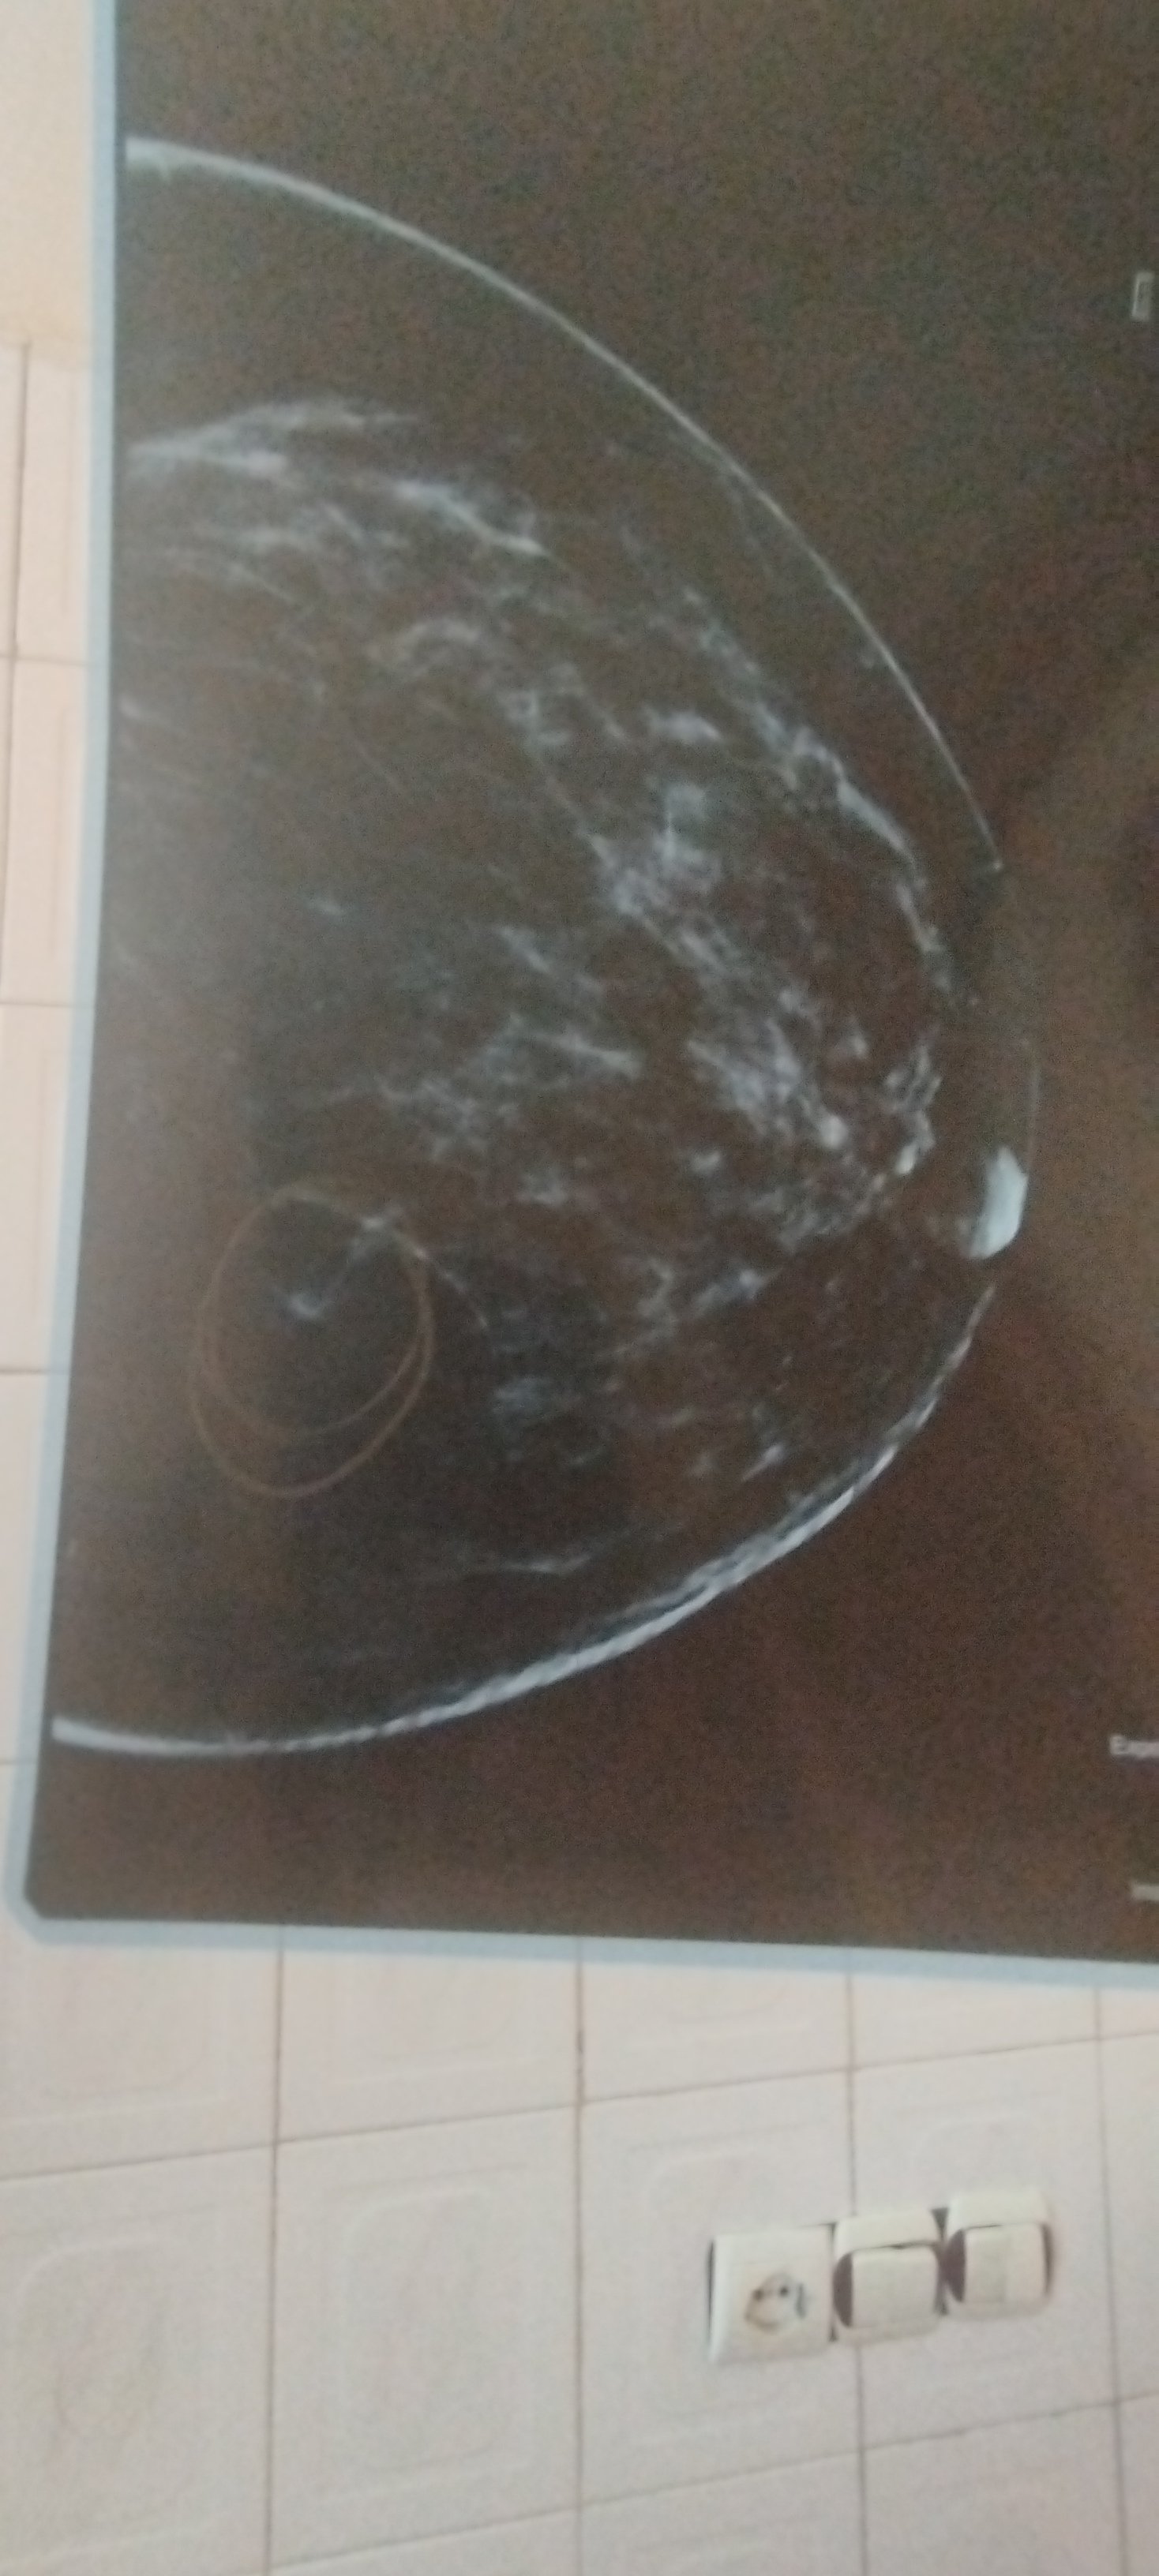

دکتر سلام وقتتون بخیر کرمی هستم ۴۸ ساله سال ۹۴ ماستکتومی راست شدم با برداشتن ۴ تا لنف ماموی سالیانه انجام میدادم مشکلی نداشتهام از سال ۴۰۳ تا موکسیفنم قطع شده و پریود میشوم در گزارش مامو ۴۰3 اسیمتری فوکال به قسمت تحتانی داخلی چپ و دو آسیمتری به قسمت فوقانی پستان چپ افزوده شده که تقاضای سونو داده شد که مورد خاصی در سونو دیده نشد. در آخرین مامو گفته یک آسیمتری به پستان چپ افزوده شده که توصیه به بزرگنمایی و سونو شده. نیاز به انجام کار خاصی هست؟ با تشکر فراوان

سلام. موارد گزارش شده، اگرچه مشکوک نیستند ولی با توجه به سابقه ی شخصی شما در ابتلا به بی این بیماری، لازم است بررسی شوند.

پیشنهاد من کلیشه ی بزرگنمایی و اگر با این شک برطرف نشد، ام آر آی سینه است.